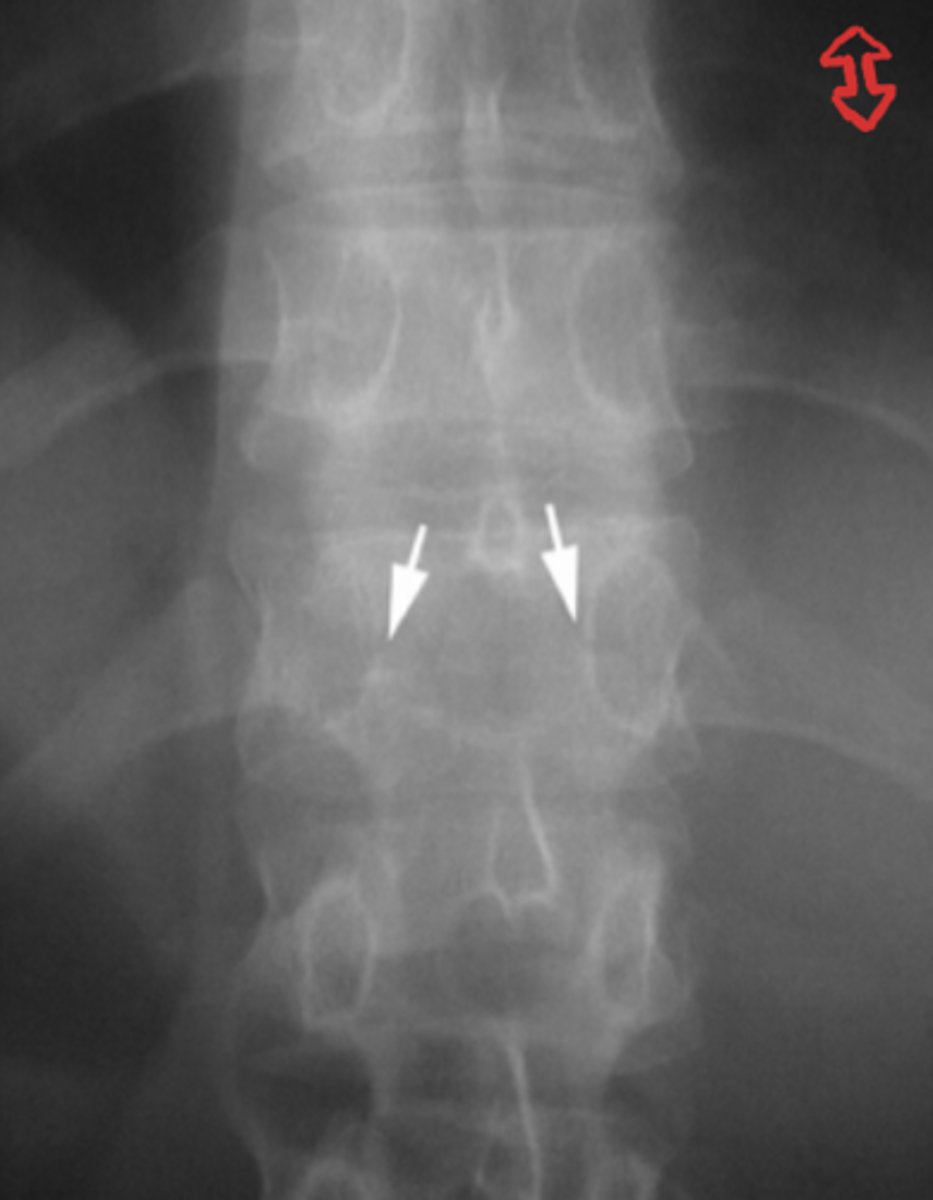

Low thoracic

What spinal level is this?

Spondylolysis

What is the issue?